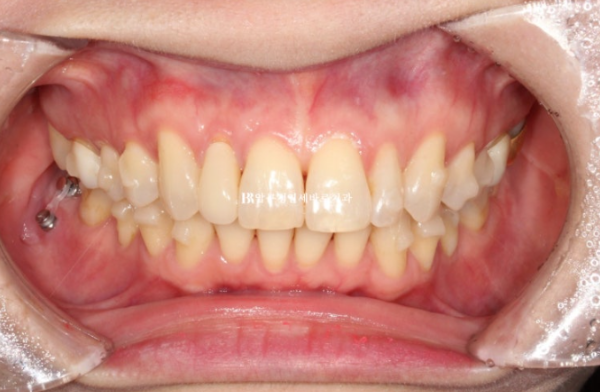

치료 마무리 후 모습입니다.

앞니가 깊게 물리는 과개교합이 개선이 되었습니다.

치간삭제로 블랙트라이앵글 사이즈를 줄일 수는 있지만 치간삭제가 과도하면 안되어서 소량의 블랙트라이앵글은 남았습니다.

치료 전 후 보겠습니다.